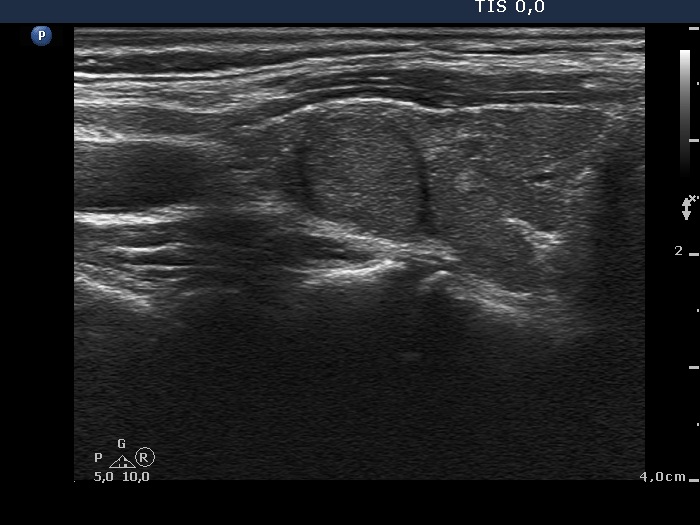

Ultrasonography. The right lobe was moderately hypoechogenic and inhomogeneous. There was a lesion in the lateral part of the lobe which presented a similar echo pattern to the extralesional part. The mass presented halo sign and showed taller-than-wide sign. There was no parenchyma in the left thyroid bed.

- The echo pattern of the nodule is almost identical to that of the extranodular part. Depending on the definition of 'normal thyroid' the nodule can be considered either isoechoic or moderately hypoechoic, the reference tissue is the non-nodular parenchyma of the specific case or a healthy thyroid, respectively. Nevertheless, the nodule is in either case an EU-TIRADS 5 nodule due to the nonparallel orientation.